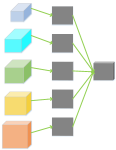

As is well known, it is hard to optimize a deep neural network due to the gradient vanish problem [28]. To alleviate the gradient vanish problem and obtain a good vessel map, we use deep supervision information in the BTS-DSN. Figure 3 gives an illustration of HED, DSN, BS-DSN and BTS-DSN. We can observe that DSN is based on HED except that there are only four side-output layers, and extra hidden layers are added in DSN for better utilizing deep supervision information. When bottom-top short connections are added to DSN, we get BS-DSN. Further, when top-bottom short connection is added to BS-DSN, we get BTS-DSN.